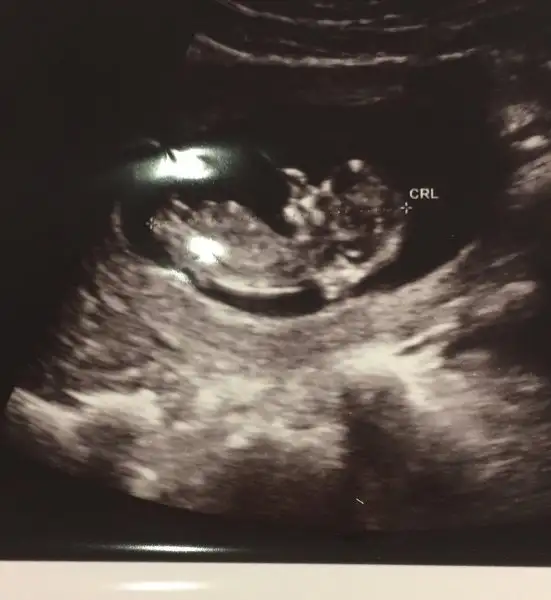

Fikir olsun diye geçen haftaki (11+5) usg görüntüsünü de paylaşayım madem

Kız nub u

Eklentiler

• FullSizeRender.webp

FullSizeRender.webp

11,6 KB · Görüntüleme: 98